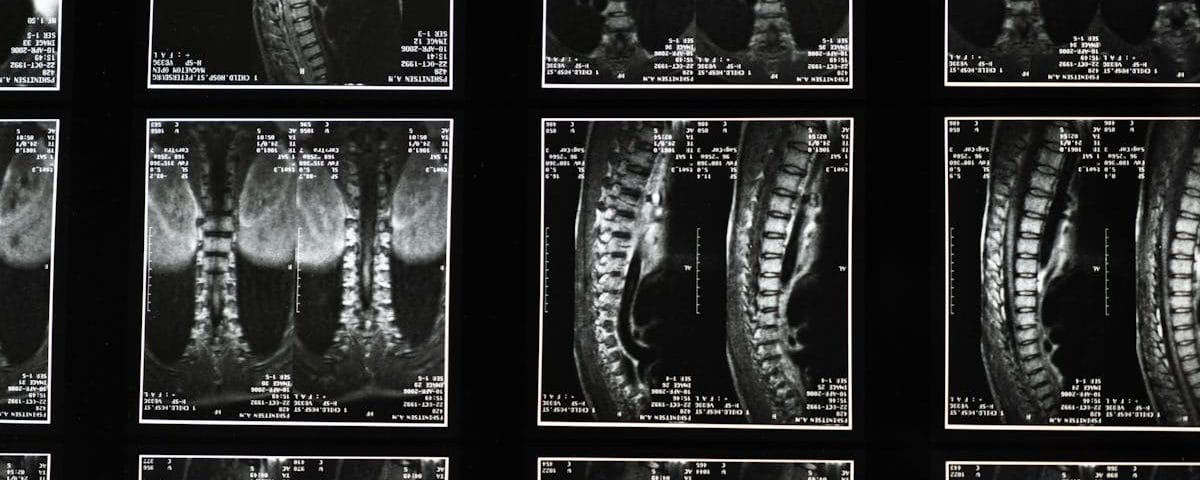

La décompression vertébrale est une approche thérapeutique prisée par de nombreux experts en santé pour traiter des douleurs dorsales chroniques et des affections associées. Cette technique non-invasive se présente comme une solution efficace pour les patients souffrant de hernies discales, de sténose spinale et d’autres troubles neuro-musculo-squelettiques. Pratiquée par des professionnels de la santé tels que les kinésithérapeutes, les ostéopathes et les chiropraticiens, la décompression neurovertébrale privilégie une approche naturelle et sans médication, offrant ainsi une alternative sûre aux traitements plus invasifs. Grâce à une expertise approfondie et à des techniques innovantes, les praticiens s’engagent à améliorer le bien-être de leurs patients en optimisant leur santé dorsale.

La décompression vertébrale se distingue par son approche non chirurgicale. Elle permet de traiter diverses conditions, notamment les hernies discales, la sténose spinale, et d’autres problèmes vertébraux. Contrairement aux solutions médicamenteuses ou chirurgicales, cette technique vise à réduire la pression sur les disques intervertébraux de manière douce et contrôlée. Cela contribue à diminuer la douleur et à favoriser une meilleure guérison.

La décompression vertébrale est une approche non-invasive visant à réduire la pression sur les disques intervertébraux et à améliorer la santé des nerfs environnants. Utilisée notamment pour traiter les hernies discales ou la sténose spinale, cette méthode peut procurer un soulagement significatif aux patients souffrant de douleurs chroniques. En choisissant un expert agréé, vous vous assurez de bénéficier des meilleures pratiques dans cette technique de pointe.